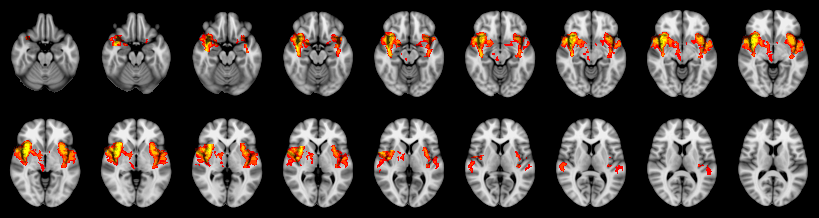

Combined

Tippett:

Fisher:

Stouffer:

Edgington:

Mudholkar–George: